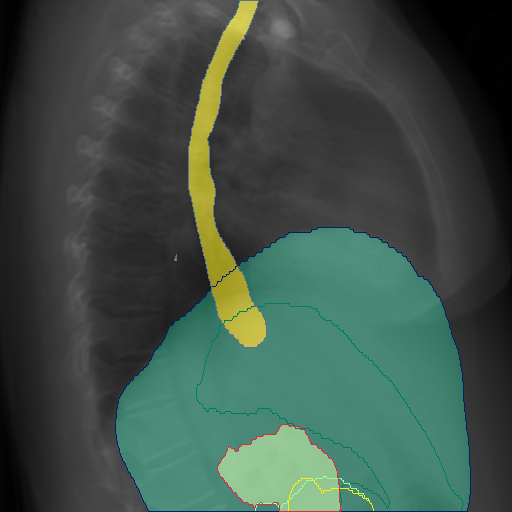

In Fig. 4, we show qualitative examples of the calculation of the cardio-thoracic-ratio for patients presenting cardiomegaly and not presenting cardiomegaly. For the case of the pathology, we see that the border of the heart is expanded, leading to a CTR above 0.7, whereas, for the absence case, the CTR is 0.4255.

In Fig. 4, we show qualitative examples of the calculation of the SCD for patients for the presence and absence of scoliosis. We can see that the vertebrae segmentation presents a noticeable curvature for the scoliosis case, leading to an SCD above 19, while for the patient with a healthy spine, the SCD is 1.125.